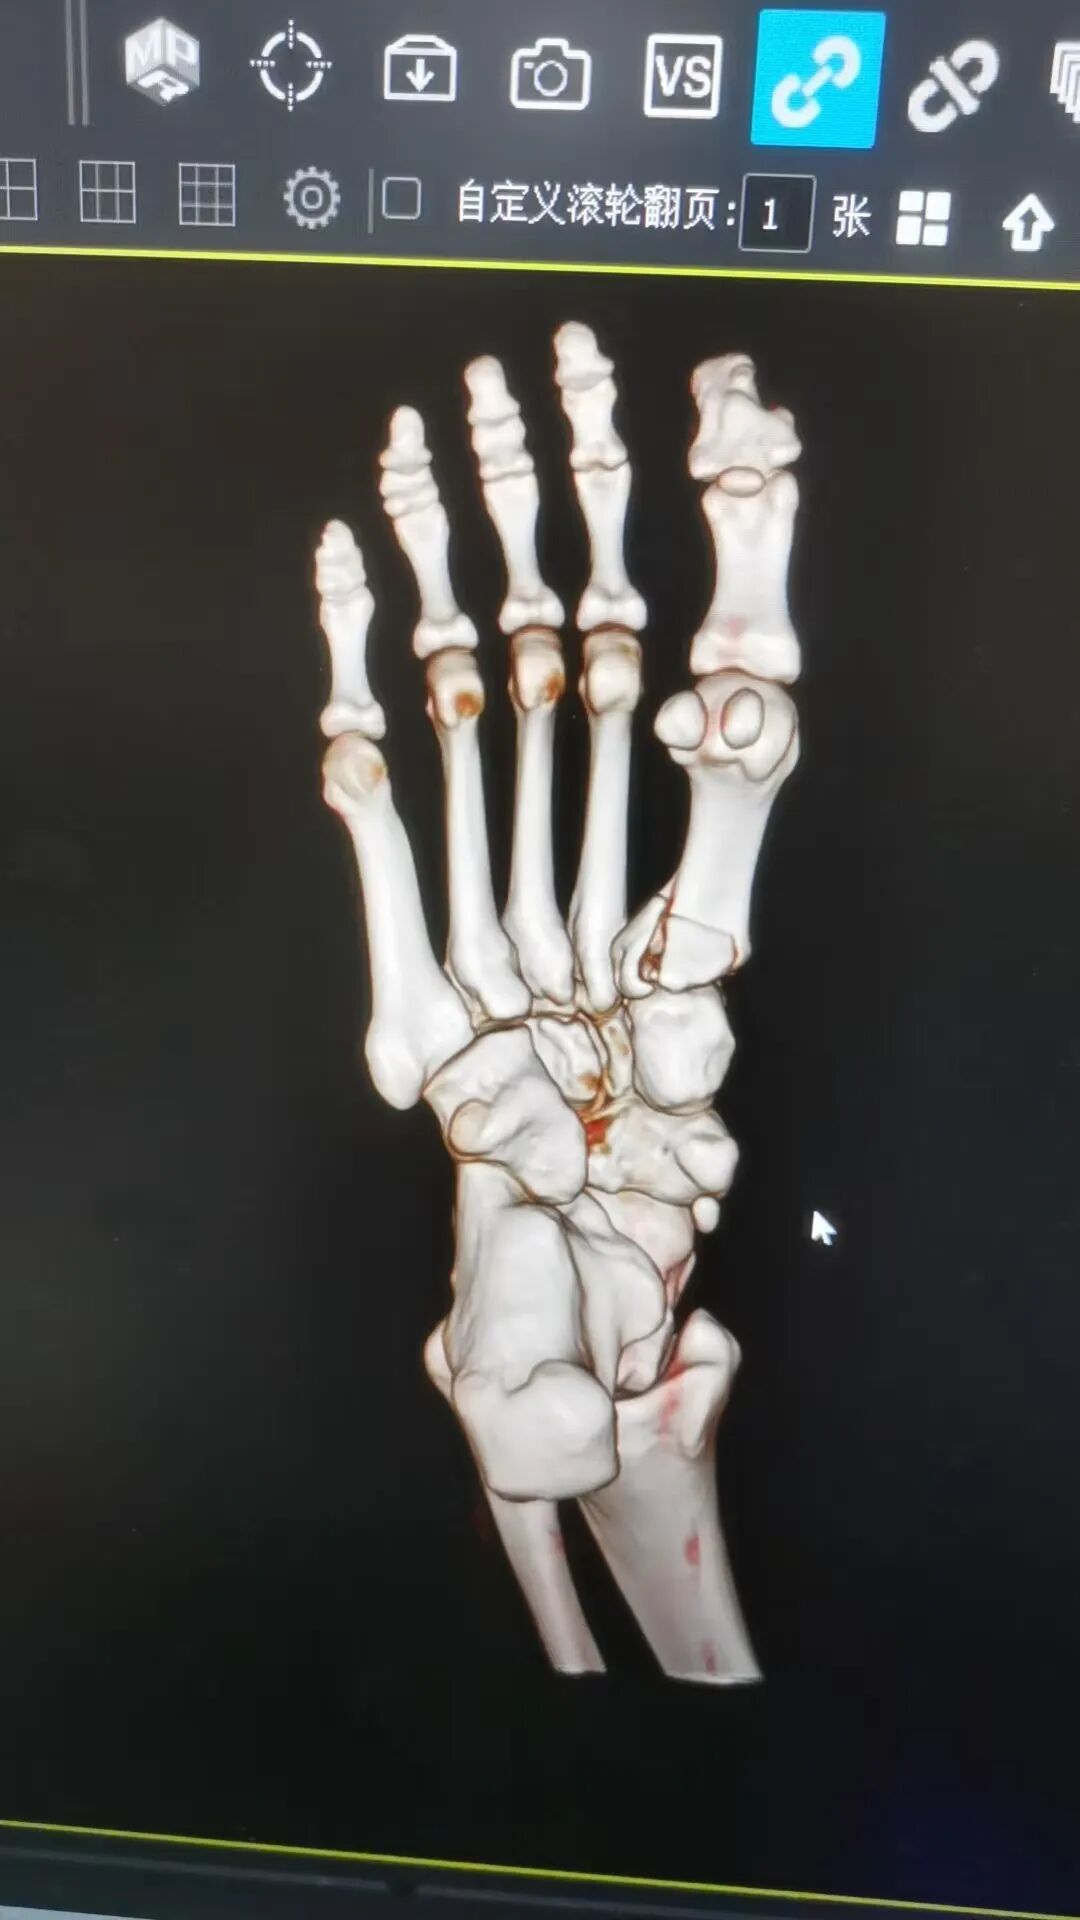

据悉,今年春节假期期间,家住南丹县的唐女士在行走时不慎跌倒,伤及右足部,伤后即感右足部呈持续性胀痛,右脚不能站立及行走,在家休息一天后,患处肿痛未缓解,遂至市中医医院骨伤科一病区就诊。经医生查体并行DR等辅助检查后,唐女士被诊断为“右足第一跖骨骨折”收治入院。

△术前